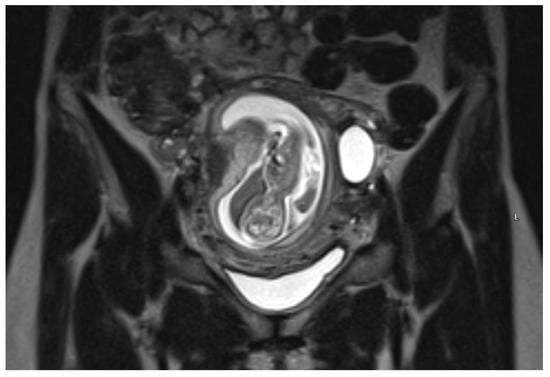

An urgent Magnetic Resonance Imaging (MRI) was performed. A 36 × 20 × 36 mm size cystic mass with T2-hyperintense wall in the left cornual region was observed. An MRI scan also showed one more fetus inside the uterine cavity with placenta located on the left lateral wall. Figure 2 The diagnosis of a heterotopic angular pregnancy in the left cornu of the uterus was established. The patient was hospitalized for further observation.

Figure 2. MRI scan of the uterus on the 13w + 3d.